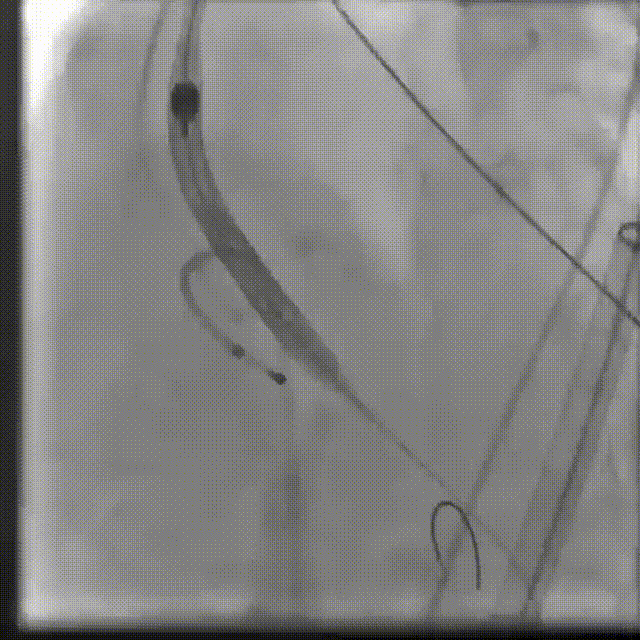

起搏心脏,预扩张主动脉瓣

球囊扩张

输送系统定位

瓣膜释放